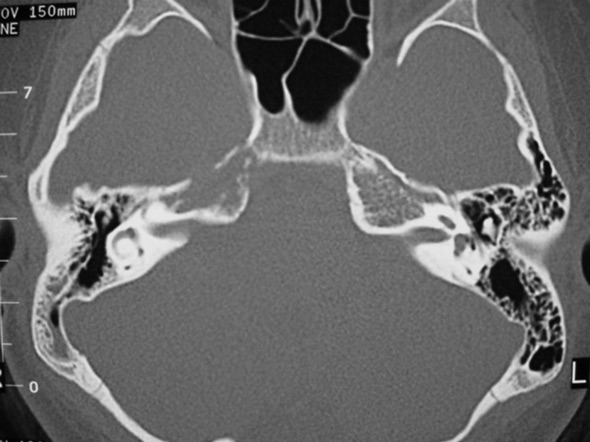

The petrous apex is a relatively inaccessible area that can occasionally harbor serious disease. Disease processes that usually cause symptoms are typically inflammatory or neoplastic in nature. Petrous apex lesions typically cause nonspecific symptoms such as headache, but as the lesion becomes more extensive, adjacent structures such as cranial nerves can become involved. A common early and specific sign of a petrous apex process is abducens palsy. Current imaging techniques can usually provide enough supplemental information to allow a focused plan of treatment. It is important to determine whether a petrous apex lesion can be observed or, if surgical treatment is required, whether a drainage or excision is required. There are various available surgical approaches to the petrous apex. The choice depends on the status of hearing function as well as the suspected pathology, which will dictate whether a drainage or excisional procedure is required.

- Summarize the types of pathology that can occur in the petrous apex, the imaging required, and proper interpretation of information so that a proper differential diagnosis can be formulated.